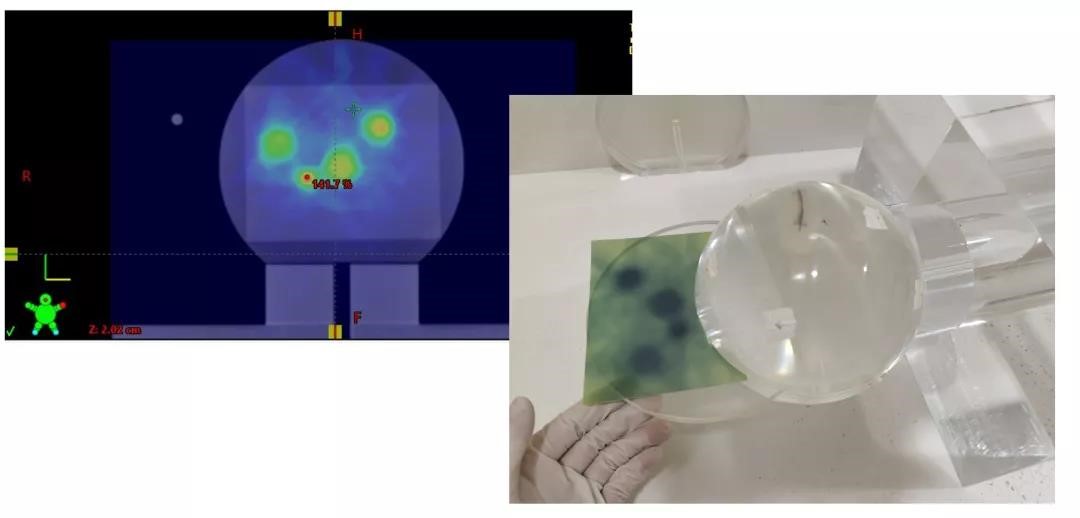

1、Winston-Lutz-Gao Test

一个等中心多靶点照射,难免会出现某些靶点距离等中心较远的情况,这时候我们怎么确保治疗的精度?其中一项很有意义的测试就是设计偏中心照射野进行Winston-Lutz测试。

在偏中心9cm处,开一个2*2cm的小野,

进行Winston-Lutz测试

使用DoseLab分析结果显示,最大误差为0.7mm,

治疗精度完全可以控制在1mm以内

使用钻石探头和头部仿真模体进行点剂量验证

胶片剂量验证